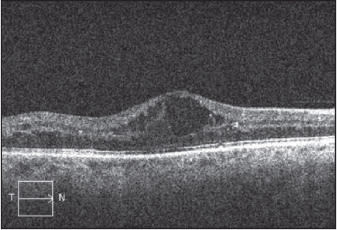

Figure 2. Preoperative SD-OCT (left ) shows significant macular edema with cystoid fluid accumulation in a patient with background DR. A one-month posoperative SD-OCT image (right) shows significant improvement in macular thickness and resolution of the cystoid spaces.